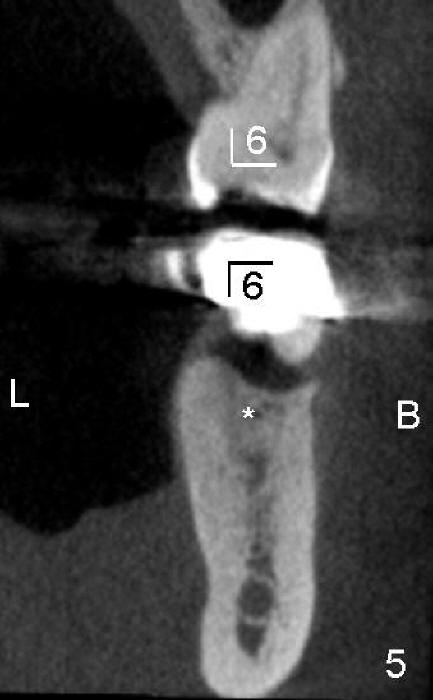

五十多岁的吴先生右下六有根分叉感染(图一),有一次到外地出差疼痛难忍拔除了,一两年后才同意植牙,图二显示已经愈合近远中(M, D)牙槽窝,六乘十七毫米植牙(图三I)好像种得很端正,其实并不完全是这样。让我们回到图二,沿着虚线做个冠状切面,显示右上六号牙以及右下六牙槽骨(图四*),与对侧六号牙冠状切面(图五)对比,右下六牙槽骨往舌侧(L)倾斜(B:颊侧),要植入长而宽的植牙,它就往舌侧倾斜(图八)。为了与对侧牙齿咬合,必须用二十度倾斜的基牙(图六A),但是临床上通过基牙而改变的角度还不够(图七),所以最后牙冠(图十C)不在植牙(I)长轴上,也就是一部分牙冠是悬臂的(*),容易造成陶瓷断裂,基牙松动。避免悬臂牙冠最好的方法便是拔牙后即刻植牙(图九),如果骨质已经吸收,植骨(图十一红色)或者骨扩张时尽量让颊侧骨板往颊侧移动,纠正植牙倾斜角度。